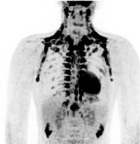

El Organismo Internacional de Energía Atómica (OIEA) a través de la Sección de Medicina Nuclear Y Diagnóstico por Imagen publicó las Series de Salud Humana Nos. 18 y 23, que tratan aspectos de la Cardiología Nuclear.